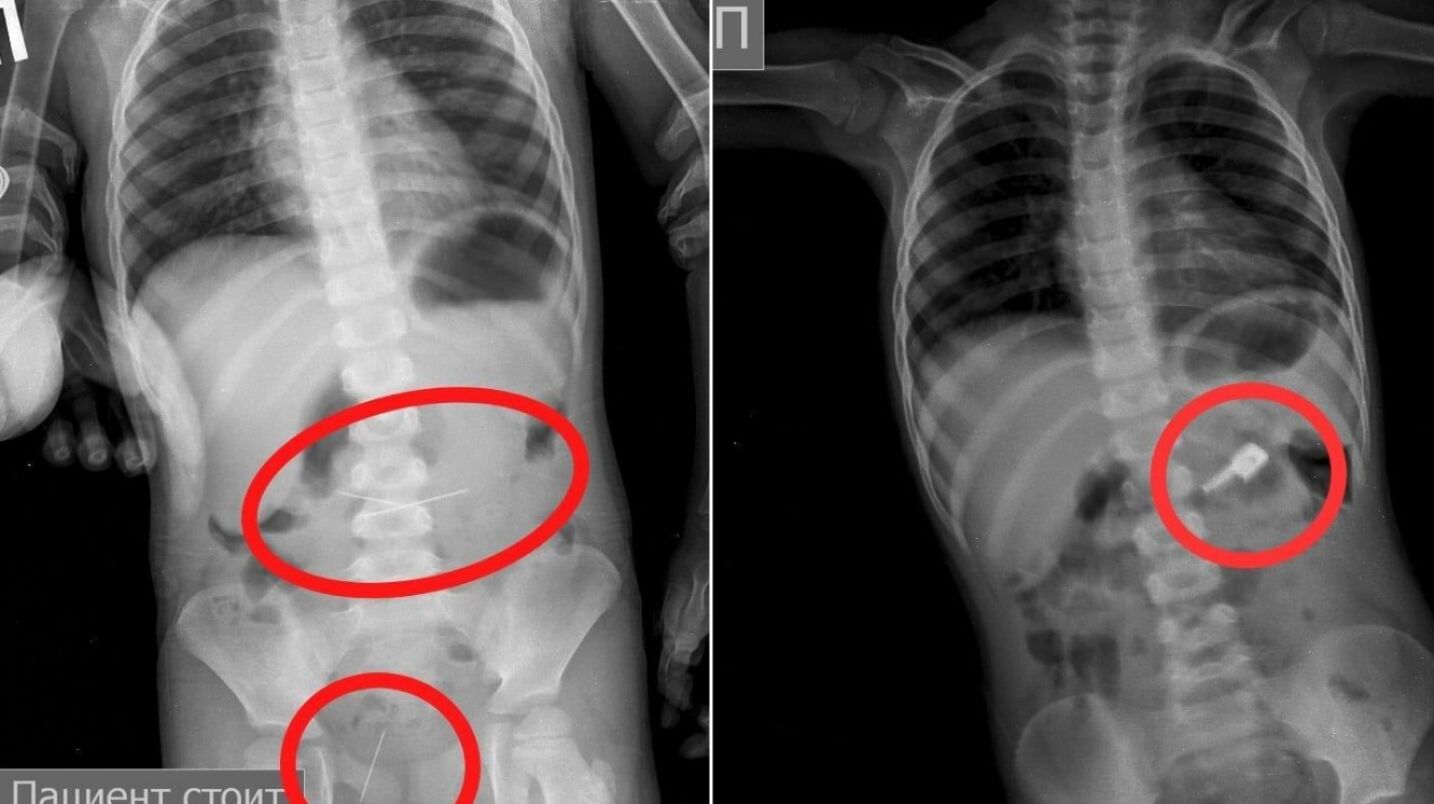

Аниқланишича, 3 ёшли боланинг онаси уни касалхонага олиб келган. Рентгенда унинг ошқозонида тикув игналари борлиги кўриниб, ҳаммаси бўлиб кичкина бемор 4 та игнани ютиб юборганлиги маълум бўлган.

Шифокорлар бир неча кун давомида эндоскопик асбоб-ускуналар ёрдамида жарроҳлик амалиётисиз игналарни олиб ташлашган.